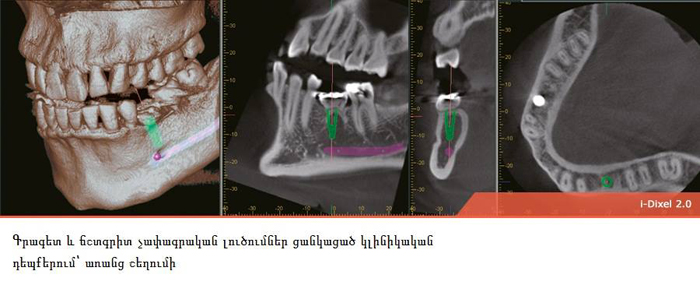

3D տոմոգրաֆիան մեծ նշանակություն ունի իմպլանտոլոգիայում, պարօդոնտոլոգիայում և էնդոդոնտիայում: Այս հետազոտության շնորհիվ բժիշկը կարող է տեսնել ստոմատոլոգիական բնույթի մի շարք խնդիրներ, ինպես նաև տվյալ պացիենտին բնորոշ անատոմիական առանձնահատկությունները. ատամի կառուցվածքը, ոսկրային հյուսվածքը, հայմորյան ծոցերը և այլն:

Թերապևտ-ստոմատոլոգի համար, նախքան բուժում սկսելը, շատ կարևոր է իմանալ, թե տվյալ պացիենտի մոտ քանի արմատախողովակից է կազմված ատամը, որպեսզի անհրաժեշտության դեպքում կատարի ճիշտ մշակում և հերմետիկ փակում: Ոսկրային հյուսվածքի ծավալի և կազմի մասին 3D տոմոգրաֆիայի օգնությամբ ստացած տեղեկատվությունը ատամների իմպլանտացիայի ժամանակ բժիշկին հնարավորություն է ընձեռում իմպլանտը ճիշտ տեղադրել: